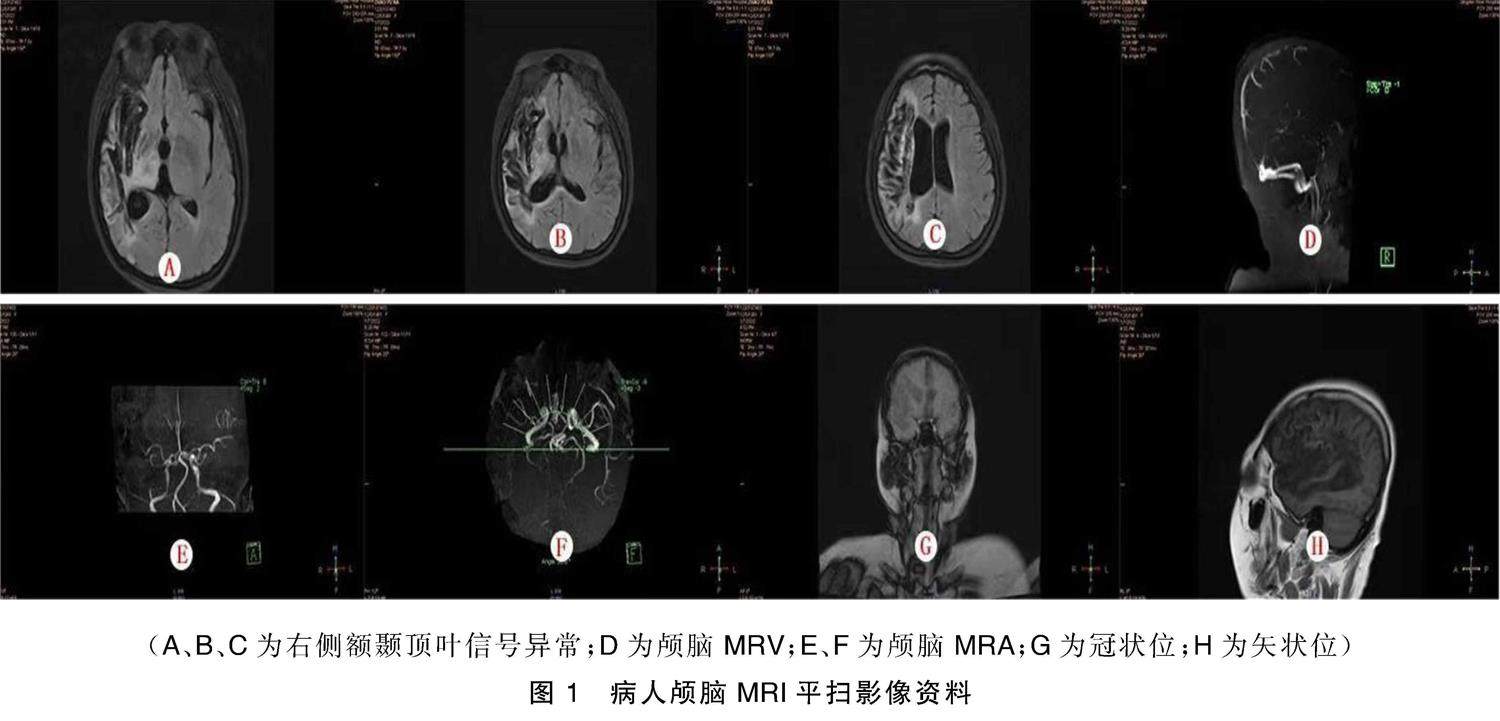

摘要 回顾性分析我科收治的1例Prader-Willi综合征(PWS) 合并脑梗死伴癫痫病例的临床资料,并对相关文献进行复习。本病例由动脉粥样硬化导致右侧大脑前动脉闭塞,后继发癫痫,确诊后进行抗癫痫、脑保护治疗,控制情况良好,PWS病人可能因动脉粥样硬化导致脑梗死,同时对PWS病人应做到早诊早治,制定个性化的系统治疗,避免继发脑血管疾病等不良事件。(剩余5213字)